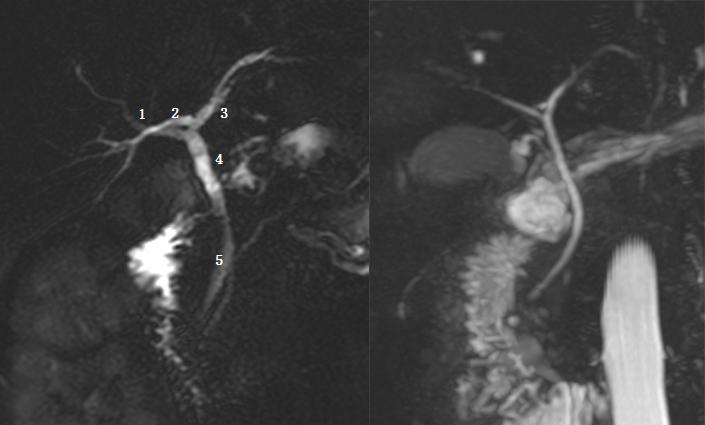

Ⅲc 型为为右后肝管汇入胆囊管。左图 1 为右前肝管,2 为肝左管,3 为右后肝管,4 为胆囊管,5 为胆总管;右图 1 为胆囊管,2 为右后肝管,箭头为胆囊结石。

Ⅳ型:右肝管汇入胆囊管。左图为胆总管远端梗阻患者,图示 1 为肝右管,2 为胆囊管,3 为肝左管,4 为胆总管。